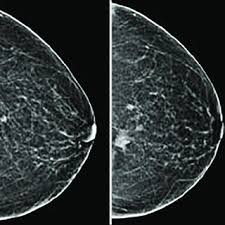

They are often caused by aging, an old injury, or inflammation and are usually benign. But radiologists can still see signs of cancer. Breast cancer can present either as an area of focal asymmetry or when advanced can even present as a new asymmetry in breast size. The photographs included on this page are the results of reconstructive procedures performed by the surgeons at the center for restorative breast surgery. Testing for breast cancer tumor markers depends on the different stages of the cancer. The look of breast cancer on a mammogram a tumor or lump will appear as a focused white area on the mammogram. Calcifications usually can't be felt, but they appear on a mammogram. A screening mammogram is used to look for signs of breast cancer in women who don't have any breast symptoms or problems. A mammogram can show breast changes such as calcifications, masses, or other symptoms that might be cancer. What does breast cancer look like on a mammogram? Calcifications are tiny flecks of calcium — like grains of salt — in the soft tissue of the breast that can sometimes indicate the presence of an early breast cancer. There are few risks associated with mammography. A mammogram image has a black background and shows the breast in variations of gray and white.

We'll show you breast cancer pictures to help you identify any physical traits of the condition. That makes it easy to detect abnormalities, which generally show up as white. Abnormalities such as cancerous tumors usually appear brighter because they are denser. Dense breast tissue appears solid. What does breast cancer look like on a mammogram? It can be any shape or size. This is why you should always talk to your doctor if you notice an unexplained change in the size of a breast. This can make it harder for your radiologist to spot signs of breast cancer, since dense tissue and tumors both look white in mammogram images.

Early signs a new mass or lump in breast tissue is the most common sign of breast cancer. What does breast cancer look like on a mammogram? That makes it easy to detect abnormalities, which generally show up as white. Any area that does not look like normal tissue is a possible cause for concern. It can be any shape or size. They are often caused by aging, an old injury, or inflammation and are usually benign. Testing for breast cancer tumor markers depends on the different stages of the cancer. Calcifications are calcium deposits within the breast tissue and they look like small white spots. This is why you should always talk to your doctor if you notice an unexplained change in the size of a breast. Calcifications usually can't be felt, but they appear on a mammogram. The first stage of breast cancer detection is the mammogram, ultrasound or breast magnetic resonance imaging exam, all of which are sensitive enough to detect breast cancer before any symptoms are noticeable.if there are any suspicious signs, then a biopsy is carried out, and only then are tests for breast. This can make it harder for your radiologist to spot signs of breast cancer, since dense tissue and tumors both look white in mammogram images. Breast cancer can present either as an area of focal asymmetry or when advanced can even present as a new asymmetry in breast size.